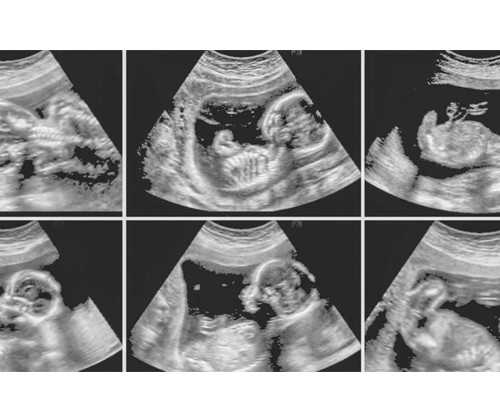

众所周知,女性一个月经周期只有一个优势卵泡排出,这个优势卵泡与精子结合,则是新生命的萌芽,试管婴儿为了确保成功几率,通常会通过药物促排,促使多个卵泡同步成熟,以保证后期移植有健康胚胎可用,这就导致很多人认为试管婴儿取卵越多越好,事实真是这样吗?

正常女性出生时两侧卵巢中有100万~200万个原始卵泡,以后逐渐退化,至青春期时,仅剩约4万个。从青春期开始,到绝经为止。女性一生中一般只有400~500个卵泡能够发育成熟并排卵。性成熟期,即育龄期,每个月会发育一批卵泡,这批卵泡中只有一个或者两个优势卵泡可以完全发育成熟并排出卵子,其余的卵泡在发育过程中自行退化消失了。而在试管婴儿过程中,通过控制性超促排卵技术,可以摆脱自然周期的限制,从而能够获得多枚优质卵子,培育出更多的优质胚胎增加患者受孕的机会。